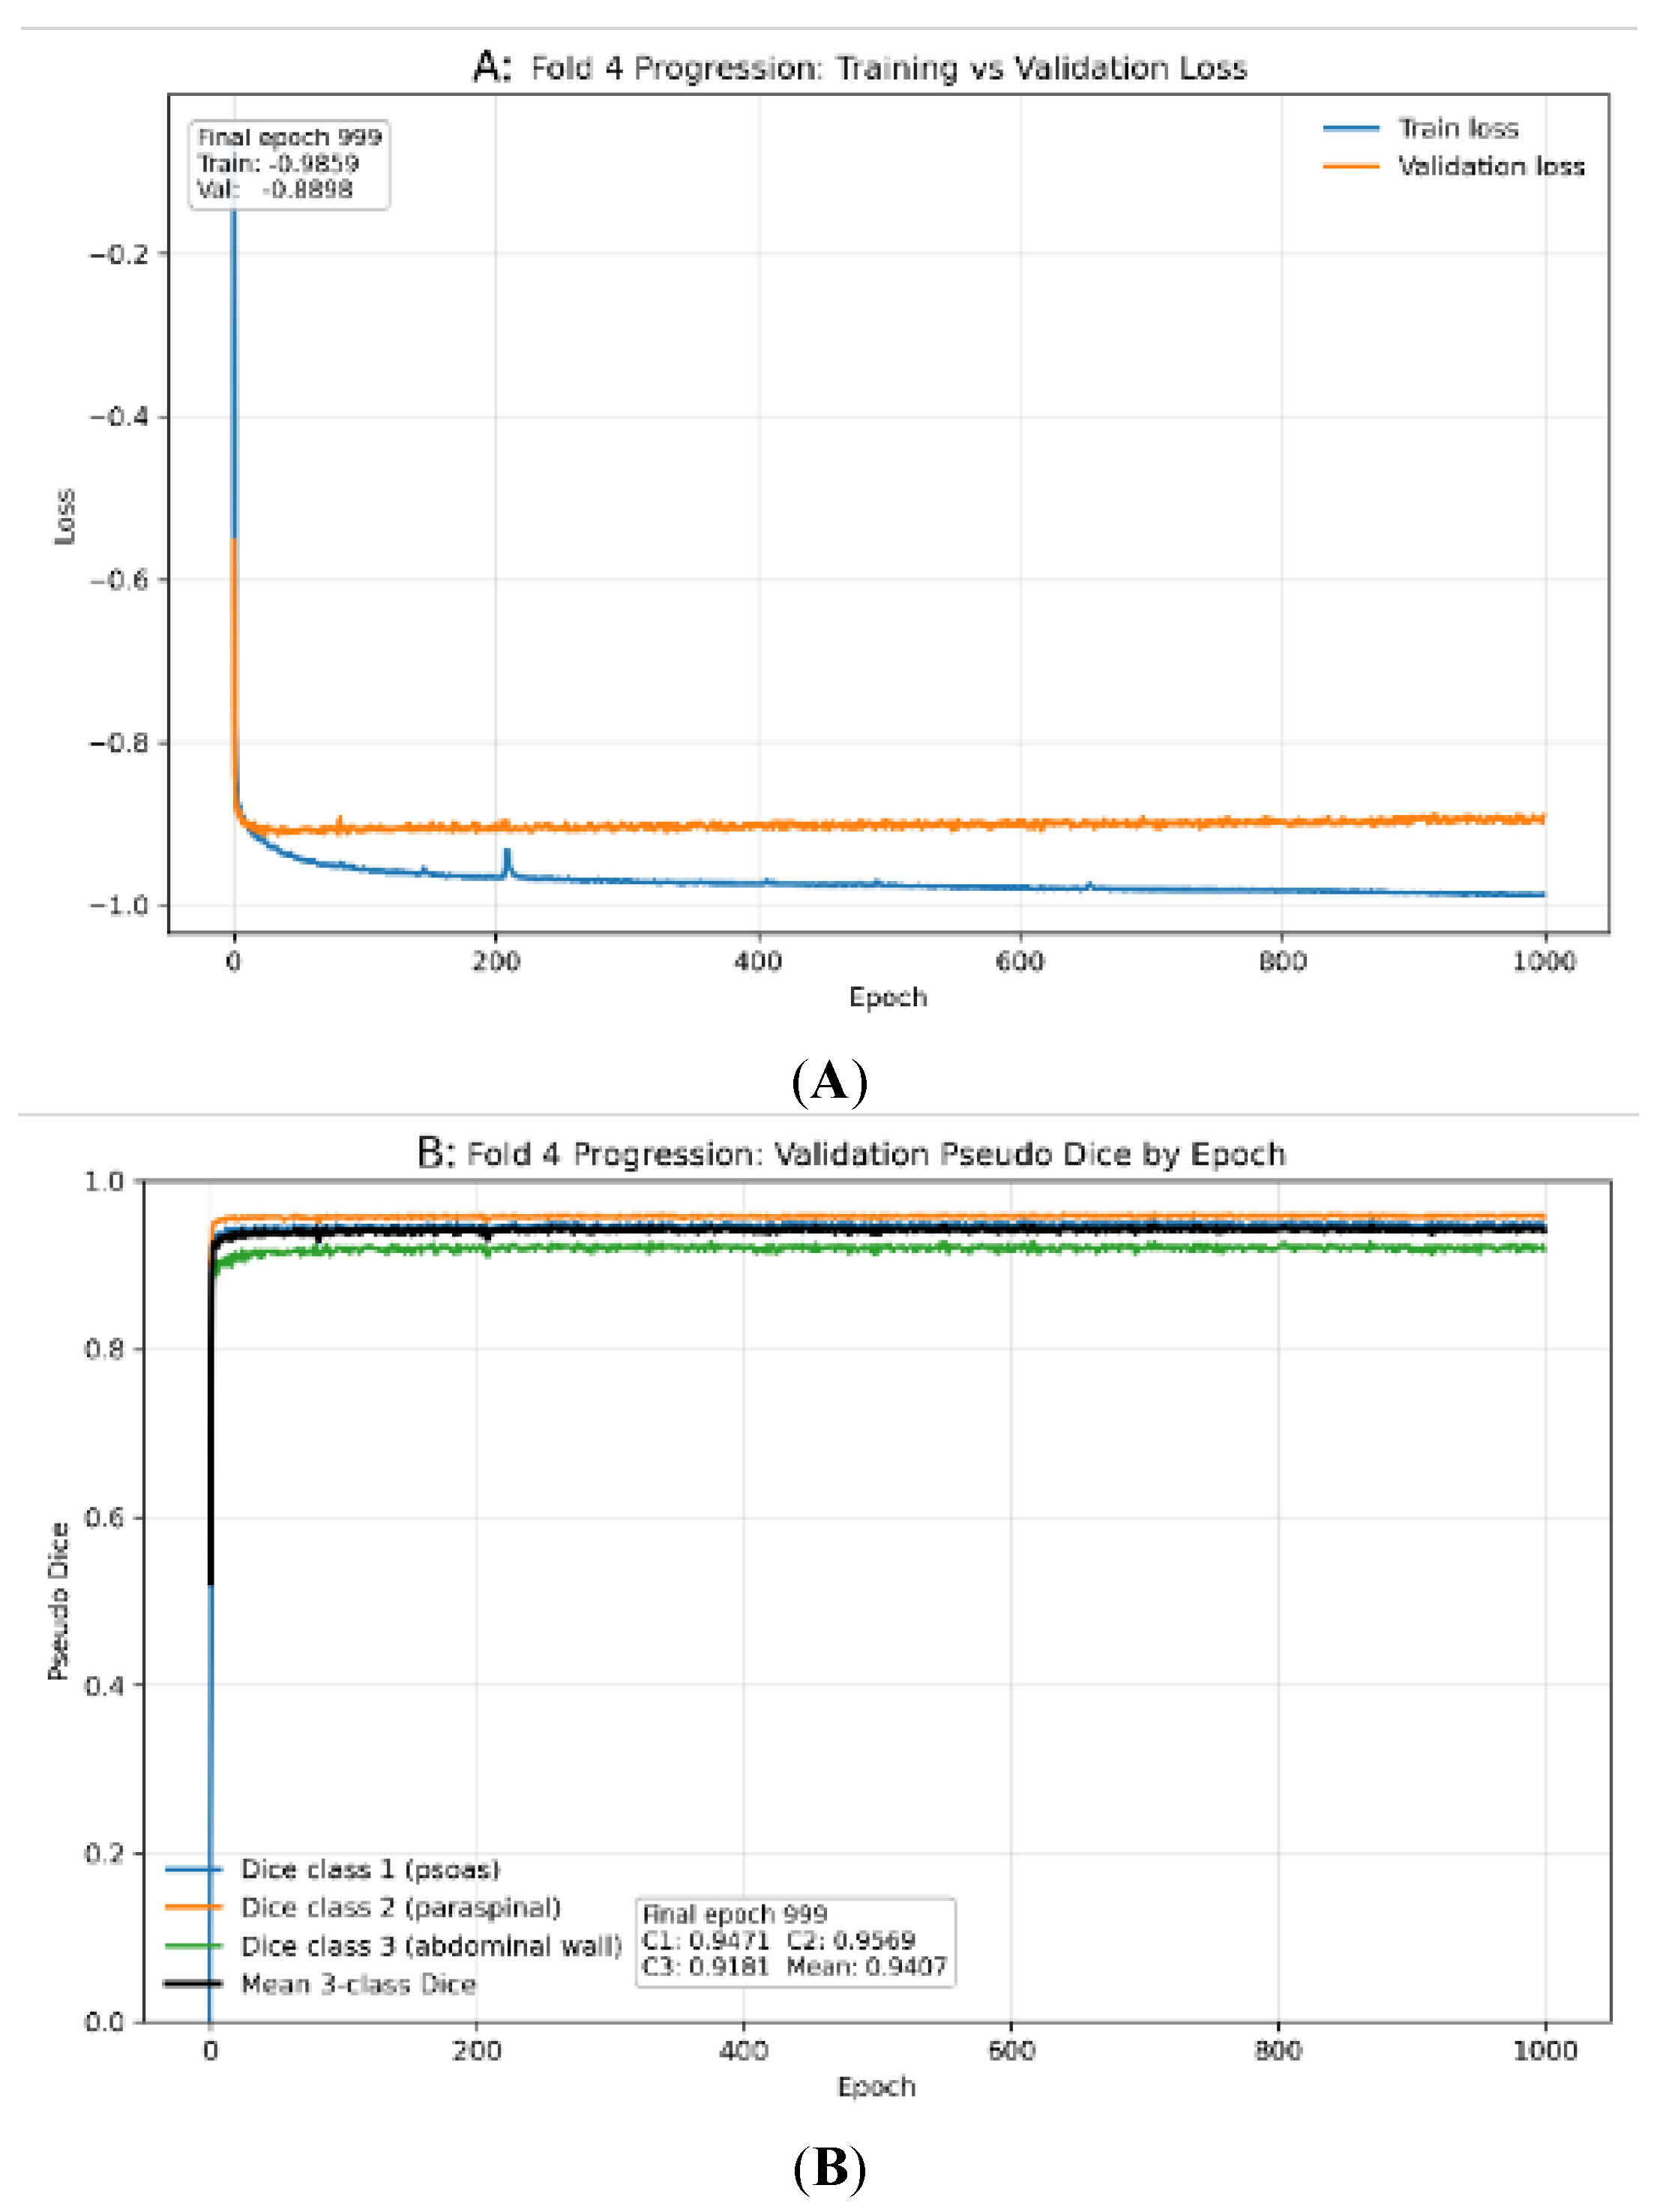

3.1. Internal Cross-Validation Performance

| Fold | Psoas | Paraspinal | Abdominal wall | Mean DSC |

|---|---|---|---|---|

| 0 | 0.932 | 0.940 | 0.898 | 0.924 |

| 1 | 0.939 | 0.956 | 0.923 | 0.939 |

| 2 | 0.941 | 0.952 | 0.908 | 0.934 |

| 3 | 0.925 | 0.935 | 0.894 | 0.918 |

| 4 | 0.946 | 0.958 | 0.919 | 0.941 |

| Mean | 0.937 | 0.948 | 0.908 | 0.931 ± 0.010 |